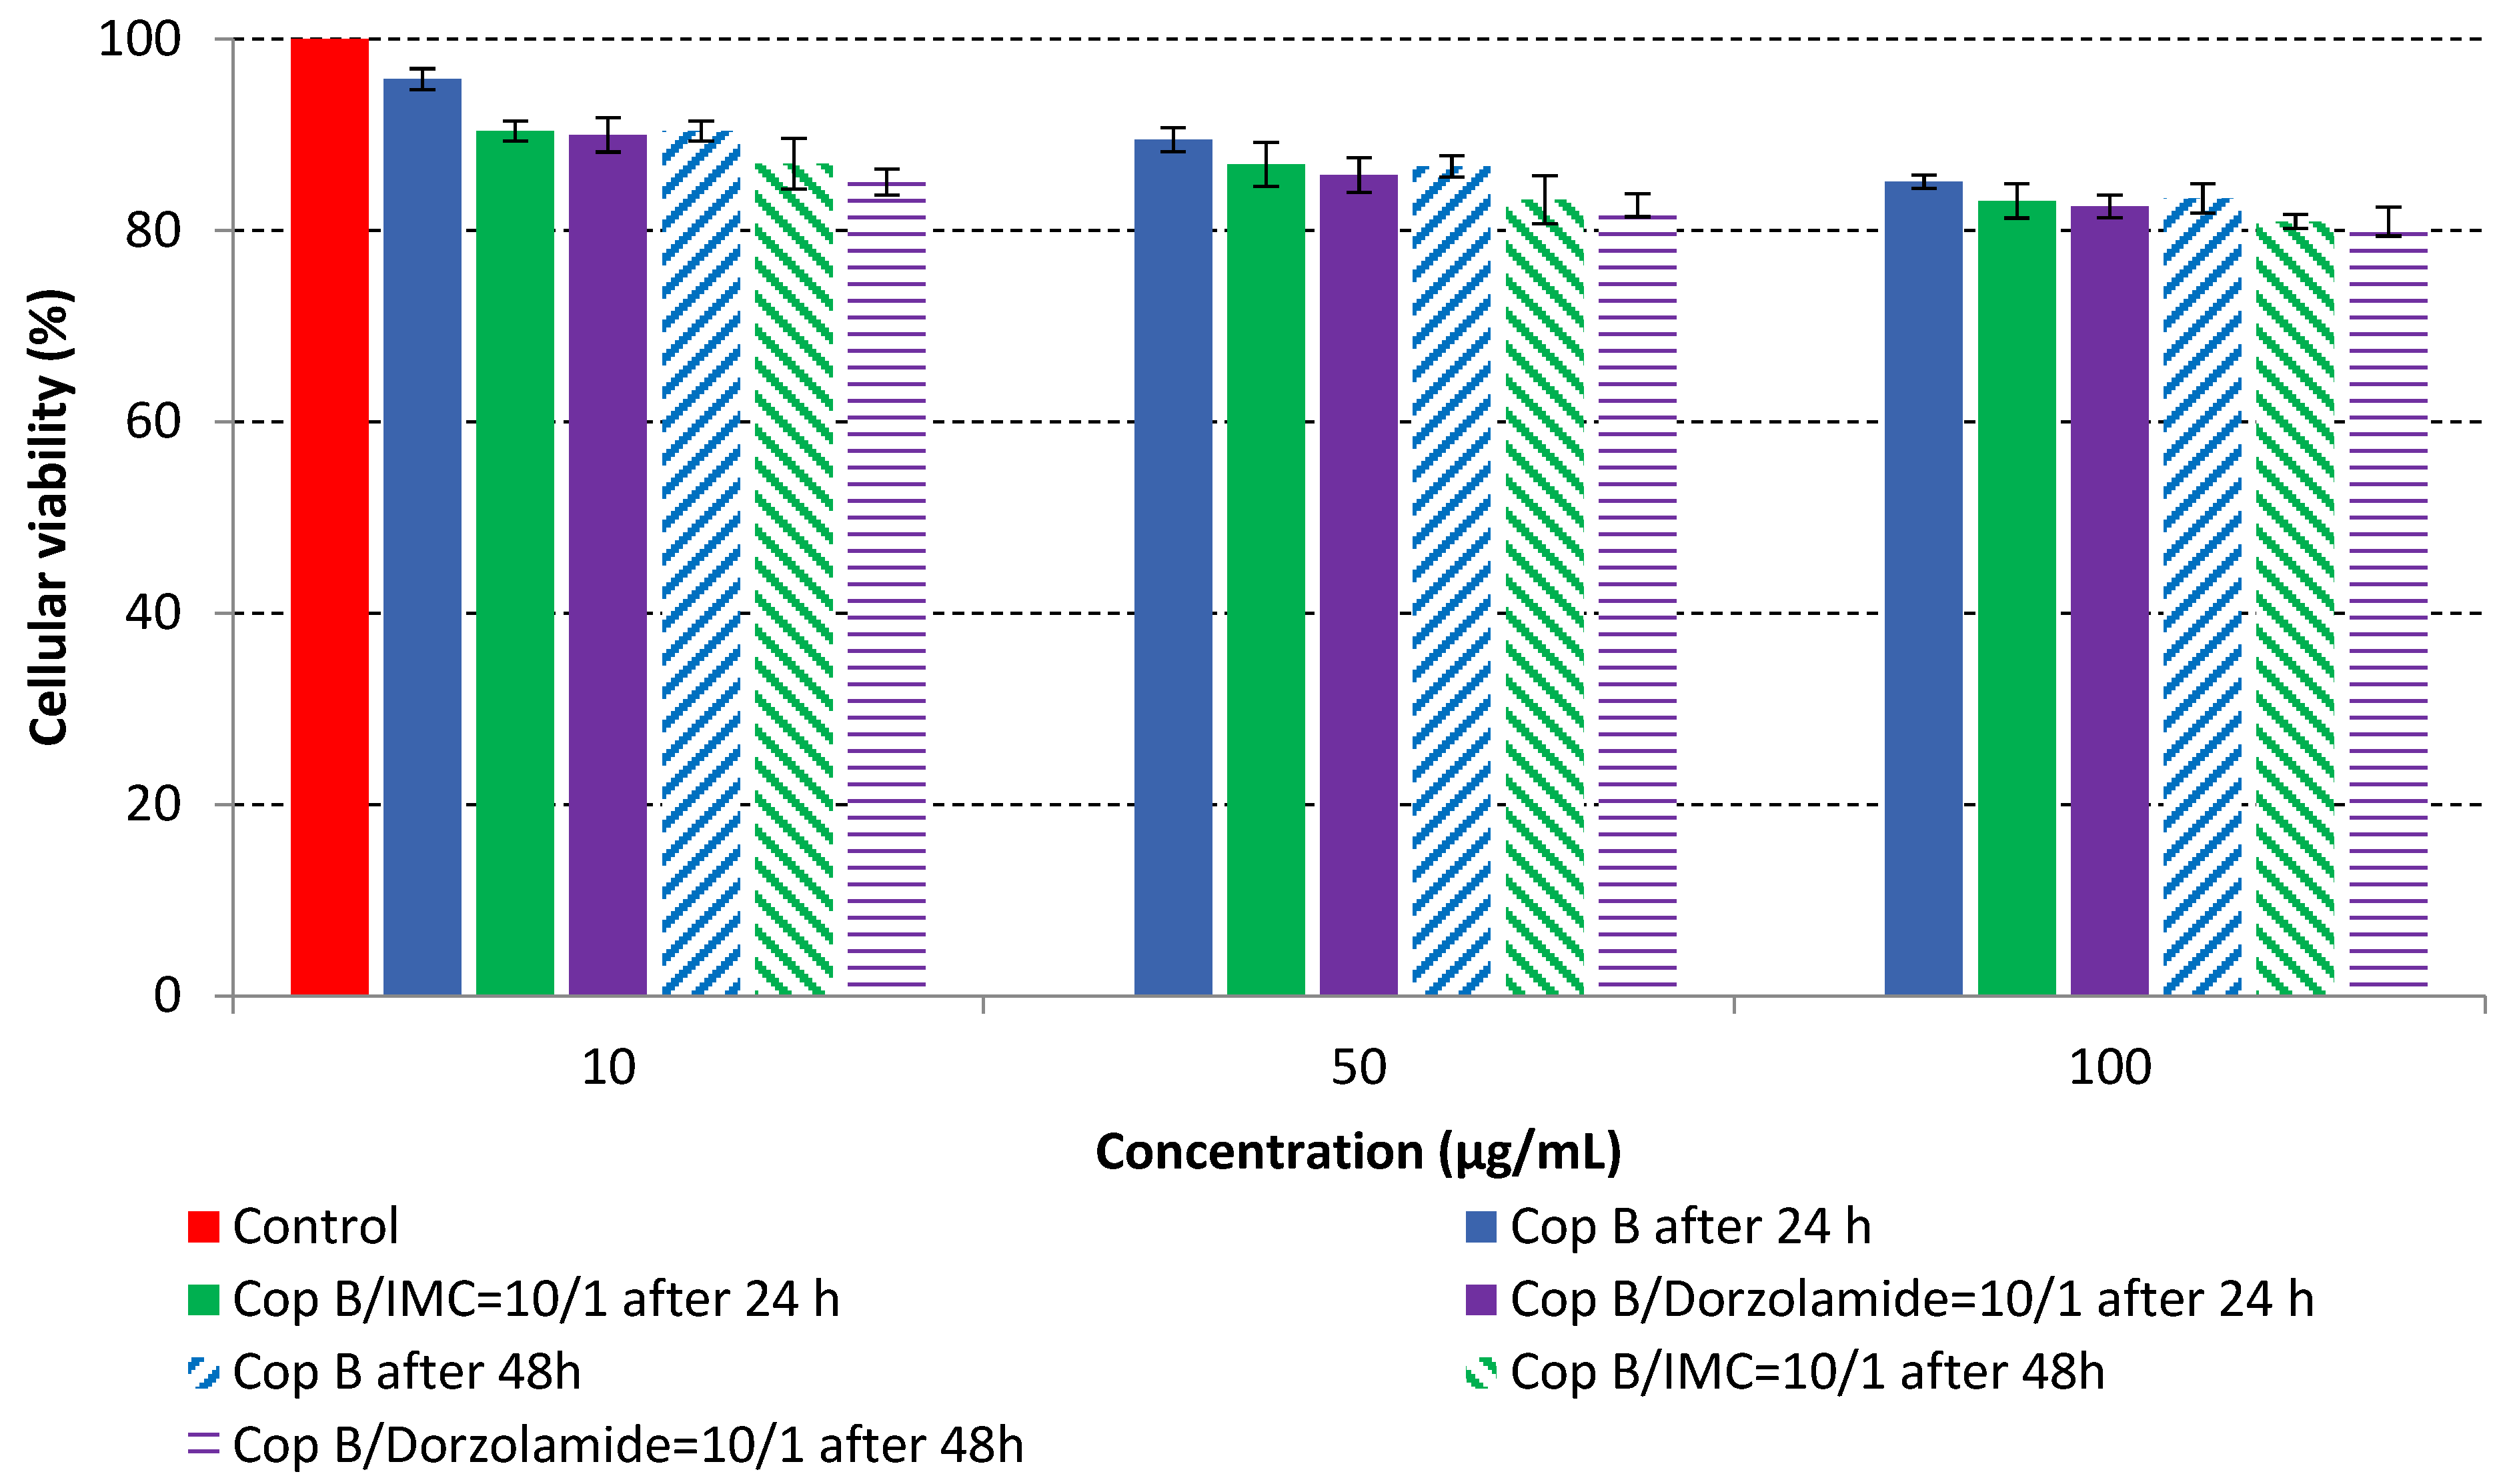

2.4. In Vitro Cytotoxicity Analysis